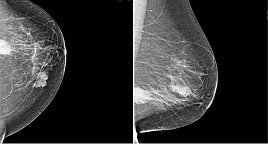

Die Mammografie ist ein Röntgenverfahren, das unter der Nutzung der charakteristischen Strahlung Schwächungsbilder der Brustdrüse erstellt, was üblicherweise in 2 Ebenen erfolgt (sog. CC und MLO-Aufnahme). Die Nutzung direkt-digitaler Systeme ermöglicht hier eine substantielle Reduktion der Strahlendosis von bis zu 40% im Vergleich zu Geräten, die erst im Nachgang ein digitales Bild erstellen oder analog verbleiben. Wir haben ein selenbasiertes Mammografiegerät in der Anwendung als einzigem entsprechend hochwertigen System in Nordthüringen und können so sehr dosissparend arbeiten. Außerdem sind bei uns 4 Röntgenassistenten nach entsprechenden Kursen als Mammafach-MTRA zertifiziert. Wir sind Partner verschiedener Brustzentren und führen im Jahr ca. 1500-2000 Mammografien durch im stationären und ambulanten Bereich. Alle Frauen mit einem Überweisungsschein und einer entsprechenden Indikation (beispielsweise einem Tastbefund oder einseitigen Schmerzen). Ein Mammakarzinom kann als Verdichtung strahlenförmig imponieren, aber auch als vielgestaltig gruppierter Mikrokalk (polymorpher Mikrokalkcluster) sowie in seltenen Fällen als Architekturstörung (siehe Beispielbilder). Ergänzend zu einer Befundung durch 2 Radiologen werden bei uns auch computerunterstützende Systeme verwandt, um eine zusätzliche Analysemöglichkeit zu entwickeln. Über diese Problematik wurden schon zahlreiche Publikationen von Prof. Malich verfasst.